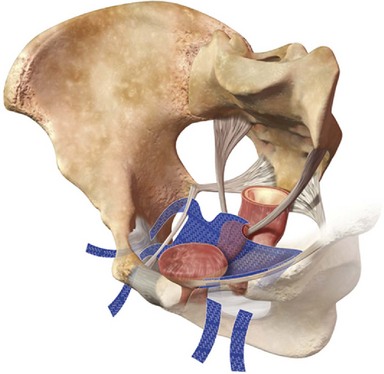

The bones of the pelvis provide the scaffold on which the soft tissue supports (muscles, ligaments, and fascia) are anchored. They include paired innominate or hip bones on either side of the sacrum, which comprise the pelvic girdle. The innominate bones are further divided into the ileum, the ischium, and the pubis. The ischial spine provides attachment for the arcus tendineus fasciae pelvis (ATFP), the sacrospinous ligament, and the coccygeus muscle (Fig. 72–1). The obturator foramen is formed by the superior pubic ramus above, the pubic body and inferior ramus medially, and the anterior border of the ischial body below (Newell, 2005) (Fig. 72–2).

The pelvic floor comprises all of the soft tissues that essentially hold the pelvic viscera in place at the base of the bony pelvis and the levator ani muscle complex. The pelvic floor is a three-dimensional structure that functions as a unit (Hurt, 2000). The pelvic diaphragm is composed of the striated pubococcygeus, iliococcygeus, and coccygeus (Fig. 72–3). The levator ani muscles are composed of the pubococcygeus and iliococcygeus. The coccygeus is also termed the ischiococcygeus and is attached to the lateral margins of the coccyx and fifth sacral segment (Mundy, 2005). It is attached laterally to the ischial spine. The iliococcygeus is attached to the ischial spine, the arcus tendineus levator ani laterally and posteriorly, the tip of the sacrum, and the coccyx. The pubococcygeus is attached to the back of the pubis, and it courses lateral to the urethra (in males it is the pubourethralis, and in females, because it forms a sling around the vagina, it is the pubovaginalis). In both men and women, fibers of the pubococcygeus attach to the perineal body (Mundy, 2005). The pubococcygeus compresses the visceral canals, which cross the pelvic floor. The puborectalis portion of the pubococcygeus helps to create the anorectal angle. Contraction of the puborectalis causes the rectoanal junction to move toward the pubic symphysis, which is critical in maintaining fecal continence (Rogers, 2003). Although the muscles are referred to separately, like other structures of the pelvic floor the boundaries are often difficult to delineate and they perform similar physiologic functions (Mundy, 2005). The posterior levator ani group (iliococcygeus and coccygeus) fuses in the midline and attaches to the coccyx. The complex formed by this fusion is the levator plate, which serves as a supporting structure for the upper vagina and cervix, This serves not only to stabilize the upper vagina in a horizontal plane but also to provide a protective mechanism preventing downward forces onto the perineal body (Wall and Menafee, 2002).